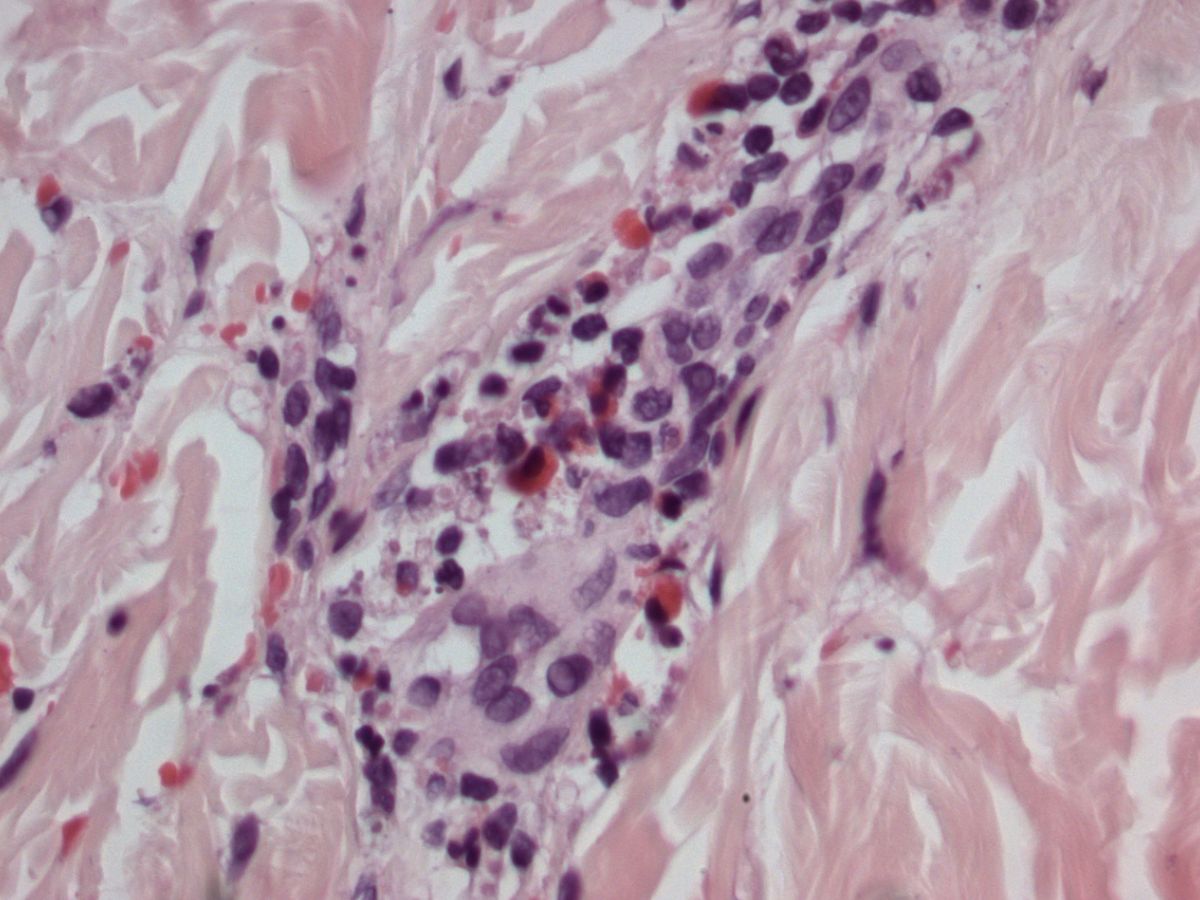

Histologie IgA vasculitis

ingescande coupe (zoom)

Bron hoge resolutie PA-foto: Kevin Kwee en Afdeling Pathologie MUMC. Klik op de afbeelding om in te zoomen.